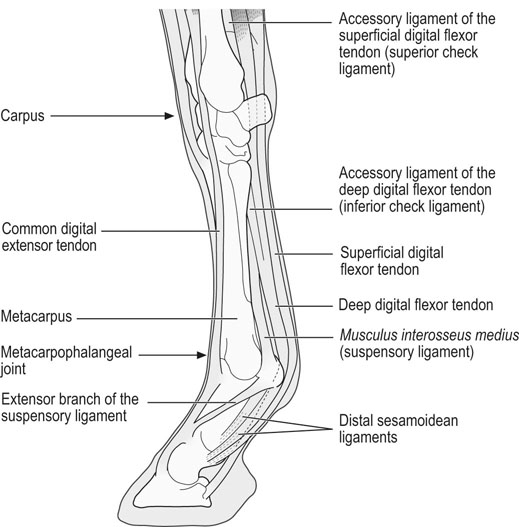

equine front limb anatomy